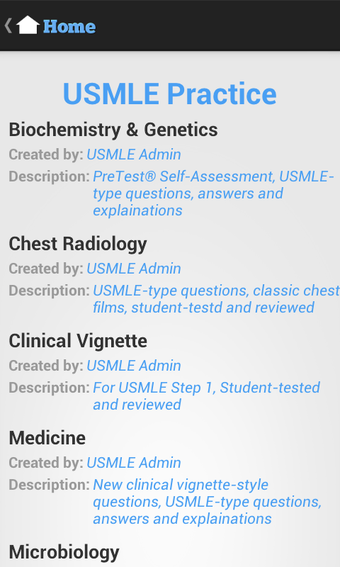

USMLE Exam Prep เป็นแอปพลิเคชัน Android ฟรีที่พัฒนาโดย quizworld ซึ่งเน้นการเตรียมความพร้อมอย่างละเอียดสำหรับการสอบ United States Medical Licensing Examination (USMLE) ให้แก่นักเรียน แอปพลิเคชันนี้ประกอบด้วยภาพพันธุกรรม ไฟล์เสียง และวิดีโอที่ครอบคลุมหลากหลายสาขา เช่น ชีวเคมีและพันธุกรรม รังสีหน้าอก วิธีการคลินิก อายุรศาสตร์ สูติศาสตร์และนรีวิทยา อายุรศาสตร์ประยุกต์ พยาธิวิทยา กุมารเวชศาสตร์ การวินิจฉัยทางกายภาพ ศัลยศาสตร์ จิตเวชศาสตร์ อาการสรีรวิทยา วิธีการคลินิก รังสีหน้าอก และการป้องกันโรค